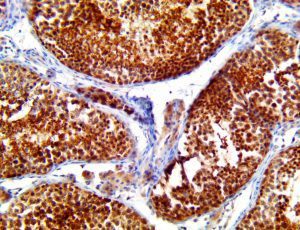

It is the ICU physician who is most likely to witness one of the deadliest manifestations of the abnormal immunological response, the cytokine storm syndrome (CSS). This response is also referred to by some as the cytokine release syndrome (CRS). CSS is characterized by continuous activation and expansion of macrophage and lymphocyte populations, which secrete large amounts of cytokines, causing the cytokine storm. This massive cytokine release is akin to hemophagocytic lymphohistiocytosis (HLH) disease, a syndrome characterized by initial unchecked and persistent activation of cytotoxic T lymphocytes and NK cells.

Clinical and laboratory manifestations of HLH include fever, enlarged liver and/or spleen, neurologic dysfunction, coagulopathy, liver dysfunction, cytopenias (i.e., low levels of erythrocytes, leukocytes, and/or platelets), hypertriglyceridemia, hyperferritinemia, hemophagocytosis, and eventually diminished NK cell activity as the immune system becomes progressively paralyzed. HLH can be familial (primary HLH) or secondary to another disease process (sHLH), such as rheumatic disease, in which it is referred to as macrophage activation syndrome (MAS, characterized by elevated ferritin).